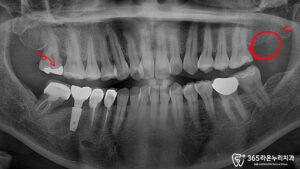

왼쪽 윗어금니가 아프고 시린 증상으로 내원하신 환자분입니다.

또한 대칭되는 위치에는 치아가 이미 상실된 상태로,

단순히 한두 개의 치아 문제가 아닌 여러 치아에 걸친 종합적인 치료가 필요한 상황이었습니다.

초진 시 정밀 검사 결과 17번 치아(상악 좌측 제2대구치)의 하방 우식이 심각한 상태로 발견되어 가장 우선적으로 치료를 시작하게 되었습니다.